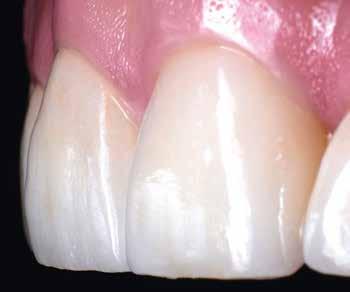

KIRÁLYKATEGÓRIA –FRONTFOG-MEGOLDÁS

Implantátum-protetikai ellátás digitális tervezéssel

Egyetlen frontfog pótlása most is – akárcsak korábban – a királykategóriába tartozik. Bármely kis formai vagy színhiba kíméletlenül megmutatkozik minden mosolynál. Ezzel hihetetlen szintet nő, vagy csökken a páciens életminősége. Stefanie Flentje esetbemutatása ismerteti, hogyan valósíthatunk meg sikerrel implantátum elhorgonyzású borítókoronát a frontterületen.

A 64 éves hölgypáciens esztétikus pótlást kívánt 21-es foga helyén, amelyet balesetet követően 2022-ben távolítottak el. Az összes foga egészséges és vitális volt, így a 21-es régióba implantátum került, amelyre cirkónium-dioxid koronát terveztünk. Az implantátum típusát, pozícióját, átmérőjét egyedi anatómiai adottságainak és az adott helyviszonyoknak megfelelően választottuk meg.

Az implantátumról készült lenyomat, valamint az alginát antagonista fertőtlenítése után szuperkemény gipszből az előírások szerint elkészültek a minták. A felső mintát a technikai implantátum körül levehető ínymaszkkal készítettük. SAM-arcív segítségével habituális okklúzióba helyeztük a mintákat. A felső mintát előkészítettük a digitális tervezéshez, enyhén megformáltuk az emergenciaprofilt, hogy tökéletes legyen a rózsa-fehér esztétika. A fogszínt – a pácienssel történt egyeztetést követően – dokumentáltuk.

Digitális tervezés

A mintát beolvastuk (D1000, 3Shape), majd megterveztük a munkát (3Shape Dental System) (6. kép). A fel -

A cirkon-oxid korona tervezése a felépítményre

Újra beolvassuk a felépítményt, normális csonkként kezelve. A sapkát anatómikus koronaként határozzuk meg, redukálva a leplezéshez. Palatinálisan „hátlemezzel” alakítjuk ki, az erőhatások jobb elviselésére. Az antagonistát is beszkennelem, meghatározom a preparációs határt és a behelyezési irányt, újra tükrözöm az 11-es fogat, és ideális pozícióba helyezem (25. kép). A helyviszonyok ellenőrzése érdekében a tükrö-

zött fog transzparensen rávetíthető a tervre (26–27. képek)

A sapkát vesztibulárisan 0,8 mm-rel redukálom, így elegendő helyem lesz a leplezéshez (28–29. képek). Palatinálisan – ahogy említettem – stabilitási okokból teli cirkonnal dolgozom. A sapkát illesztem a megfelelő nyerstömbbe, kimarom, majd éjjel szinterezem. A következő nap felpasszítom a vázat. Ezzel együtt még egy behelyező segédelemet is terveztem a felépítményhez, műanyagból (PMMA) kimartam, kiegészítve egy elfordulásgátlóval a 22-esen. A segédelem biztosítja a felépítmény tökéletes és problémamentes illesztését a szájba. Okkluzálisan végül még nyílást készítek a csavarozáshoz.

30. kép: Nehéz esetekben legtöbbször két vázat készítek különböző anyagból. A közvetlen összehasonlítás jól mutatja a cirkonok különböző transzlucenciáját. Balra: DD cube One A2; jobbra: DD Bio ZW iso A2.

tes, a paraméterek egymáshoz igazítottak, nincs szükség a fáradságos passzításra (31. kép). Csak a széleket kell még kicsit elvékonyítani. Elsőként az egyedi Liner-égetés következik, amely során már enyhe színkorrekciók is végezhetők. Utána jön az első és második dentinégetés, a végső leplezési fázist megelőzve (Creation ZI-F, Creation Willi Geller) (32–34. képek). Ez egy alacsony égetési hőmérsékletű, földpáttartalmú cirkon-oxid leplezőkerámia. Különösen robusztus, hőtágulása tökéletesen illeszkedik a cirkónium-dioxidéhoz, fénytörése és tükrözése természetes hatású3. A két korona leplezésben, formában és transzparenciában enyhe különbséget mutat (35. kép). Egy frontfog mindig nagy kihívás. A nagymetszők ráadásul az „első sorban táncolnak”, őket látjuk meg először.

Cirkon-oxid korona és leplezés

Nehéz eseteknél legtöbbször két vázat készítek különböző anyagokból. Itt is készült egy DD cube One A2-es nyerstömbből, a másik pedig DD Bio ZW iso A2 nyerstömbből (30. kép) A közvetlen összehasonlításban jól látható a két anyag fényáteresztése közötti különbség. A két váz illeszkedése tökéle-

enyhén anémiás (vérszegény – a ford.), de gyorsan újra telítődik, tökéletesen illeszkedve a szituációhoz (36–42. képek)

A páciens a DD cube One koronát választotta, ami szín és transzparencia szempontjából is nagyon harmonikusan illeszkedett a teljes képhez (43–44. képek)